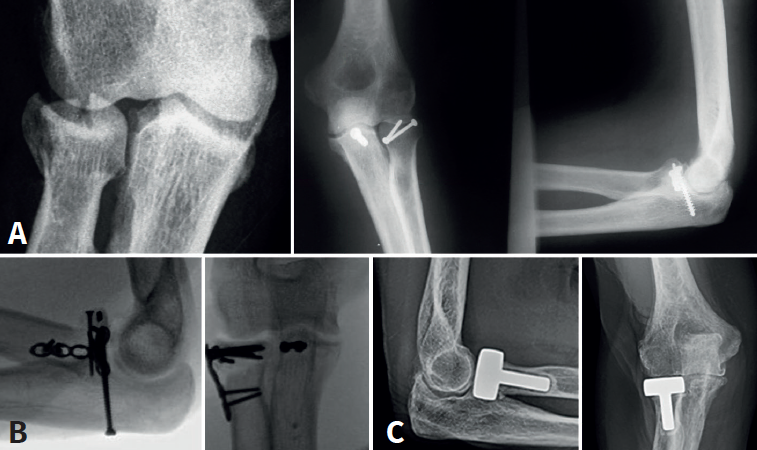

Tratamiento de la fractura de la cabeza radial

El tratamiento de la fractura de la cabeza radial es crucial para la estabilidad lateral del codo(12). El manejo depende del grado de conminución; en nuestro caso nos basamos en la clasificación de Mason (1954) y Johnston (1952)(13):

- Mason I: son aquellas fracturas sin desplazar o mínimamente desplazadas (< 2 mm) y sin bloqueo mecánico en la pronosupinación. El manejo adecuado sería conservador. En aquellos casos en los que exista un fragmento óseo (< 20%) que podría comprometer la recuperación postoperatoria se podría optar por una resección de este.

- Mason II: fracturas desplazadas > 2 mm o anguladas, y que podrían presentar un bloqueo mecánico a la rotación del antebrazo. Se opta por un tratamiento quirúrgico mediante reducción abierta y fijación interna con tornillos canulados o placas bloqueadas de bajo perfil(14).

- Mason III: fracturas conminutas, desplazadas, con bloqueo mecánico a la rotación y potencialmente irreparables. La fijación de aquellas fracturas de la cabeza del radio en 3 partes (diáfisis y 2 fragmentos articulares) es propensa a un fracaso temprano de la fijación, a una falta de consolidación y a una rotación limitada del antebrazo(15). Es por ello por lo que, en estos casos, puede ser preferible la resección de la cabeza radial seguida de la colocación de una prótesis modular. Doornberg et al.(16) han sugerido que el borde lateral de la coronoides es un punto de referencia útil para dimensionar la cabeza del radio y, en general, la prótesis no debe quedar más de 1 mm proximal a este punto de referencia (Figura 5).